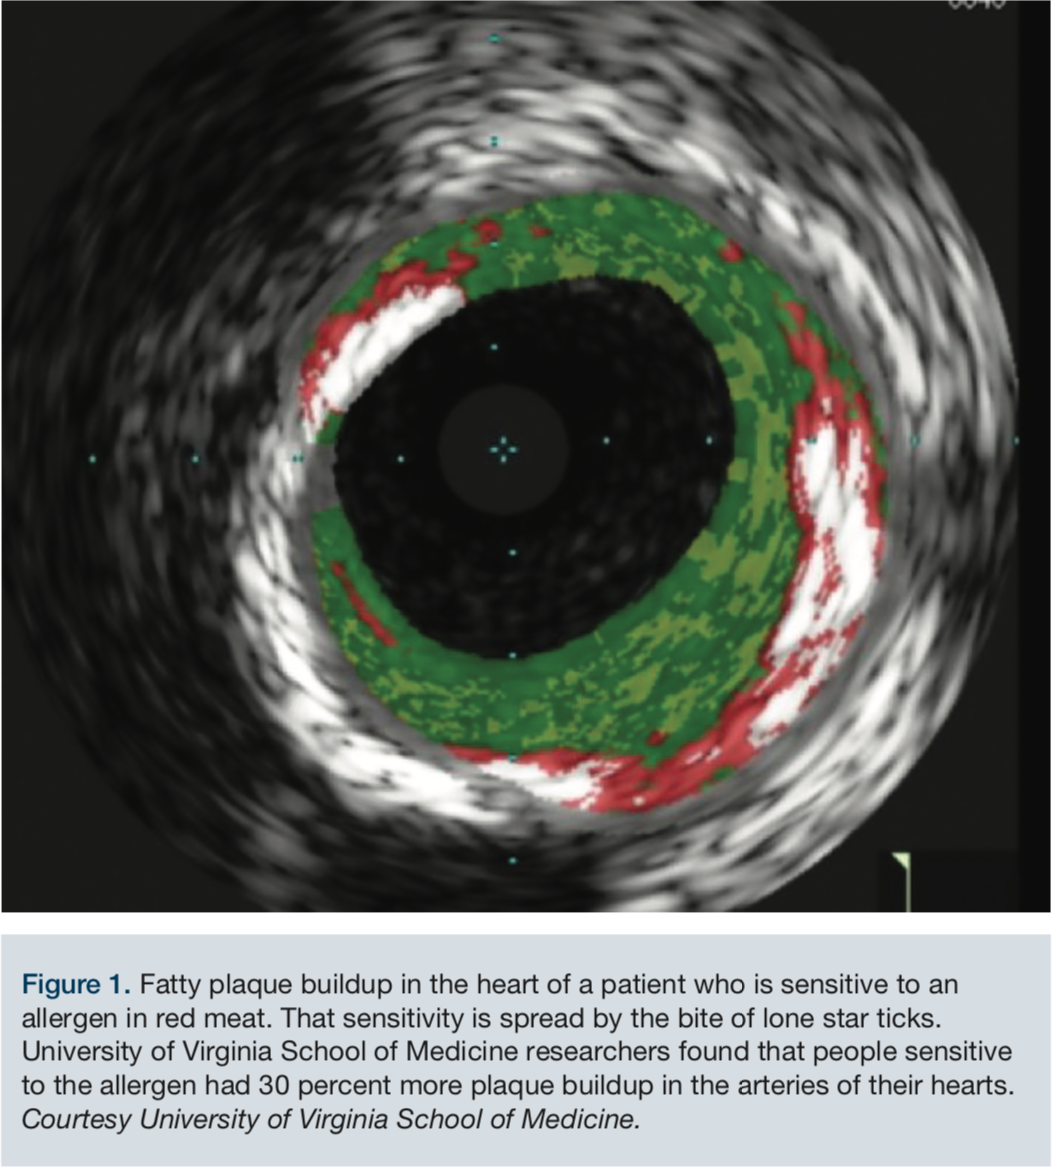

From newsroom.uvahealth.com

TickBorne Meat Sensitivity Linked to Heart Disease Meat Sensitivity Symptoms Hives or an itchy rash digestive upset such as nausea , vomiting , heartburn , indigestion , diarrhea , and severe stomach pain Common symptoms of a meat allergy can include: Symptoms of meat allergy can vary from person to person, and you may not always experience the same symptoms during every reaction. Symptoms of a red meat allergy can. Meat Sensitivity Symptoms.

From www.hmpgloballearningnetwork.com

Meat Sensitivity Spread by Ticks Linked to Heart Disease Meat Sensitivity Symptoms Hives or an itchy rash digestive upset such as nausea , vomiting , heartburn , indigestion , diarrhea , and severe stomach pain Meat allergies may also develop at various ages. Common symptoms of a meat allergy can include: Symptoms of a red meat allergy can include: Allergic reactions to food can affect the skin, respiratory tract, gastrointestinal tract, and. Meat Sensitivity Symptoms.